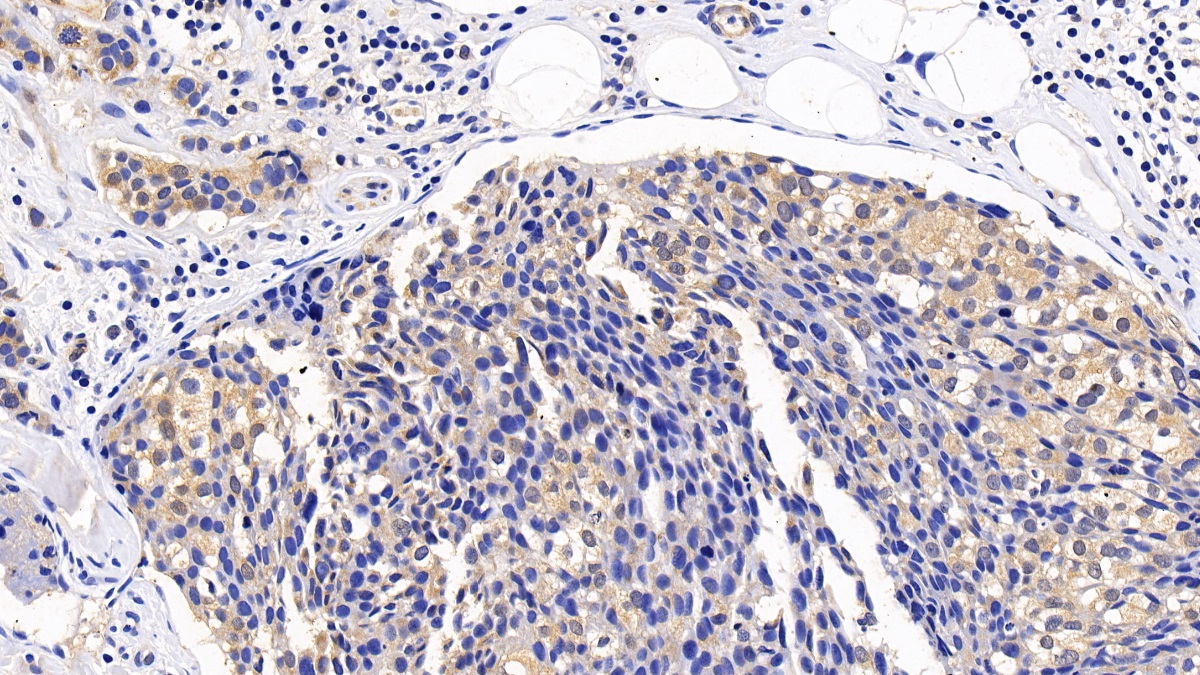

Polyclonal Antibody to Tuberous Sclerosis Protein 1 (TSC1) (PAC813Hu01)

| Название антигена | Tuberous Sclerosis Protein 1 (TSC1) |

| Валидировано для | IHC WB Иммуногистохимия; Вестерн-блоттинг |

| Рекомендуемые разведения | WB: 0.01-2 мкг/мл; IHC: 5-20 мкг/мл; ICC: 5-20 мкг/мл; Оптимальное разведение определяется конечным потребителем |